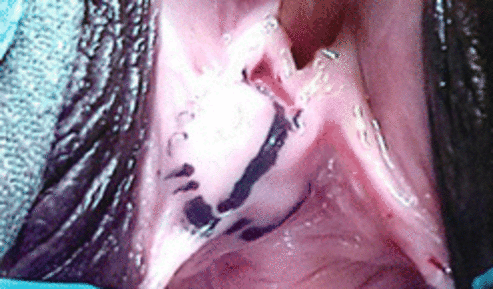

Пациентката веднага беше подготвена и отведена в операционната, и поставена под обща анестезия. След като пациентката бе поставена в гинекологична позиция, обилно количество гноевидна течност с неприятна миризма спонтанно се отдели от матката заедно с обилни количества газ във влагалището. Последва раждане на цял плод с вид на начална мацерация. След раждането на плацентата, маточната кухина се абразира с помощта на голяма кюрета на Бум и вакуум канюла № 12, под ултразвуков контрол. Поради мековитостта на матката и започналото обилно кървене се поставиха 800 µg мизопростол пер ректум. След около 2-3 минути матката се контрахира и кървенето спря. При контролния ултразвук не се откриха останали части от плод и плацента. Въпреки наличието в началото на газ във влагалището, в края на манипулацията ултразвука не установи наличието на газови частици в кухината на матката.